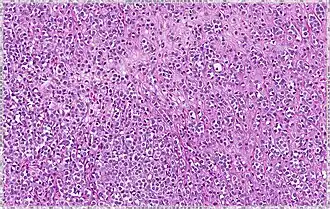

| Pleomorphic | Classical-appearing but with pleomorphic cells. It may include signet-ring cells, or plasmacytoid cells (pictured) which have abundant cytoplasm and eccentric nuclei. | ![]() |